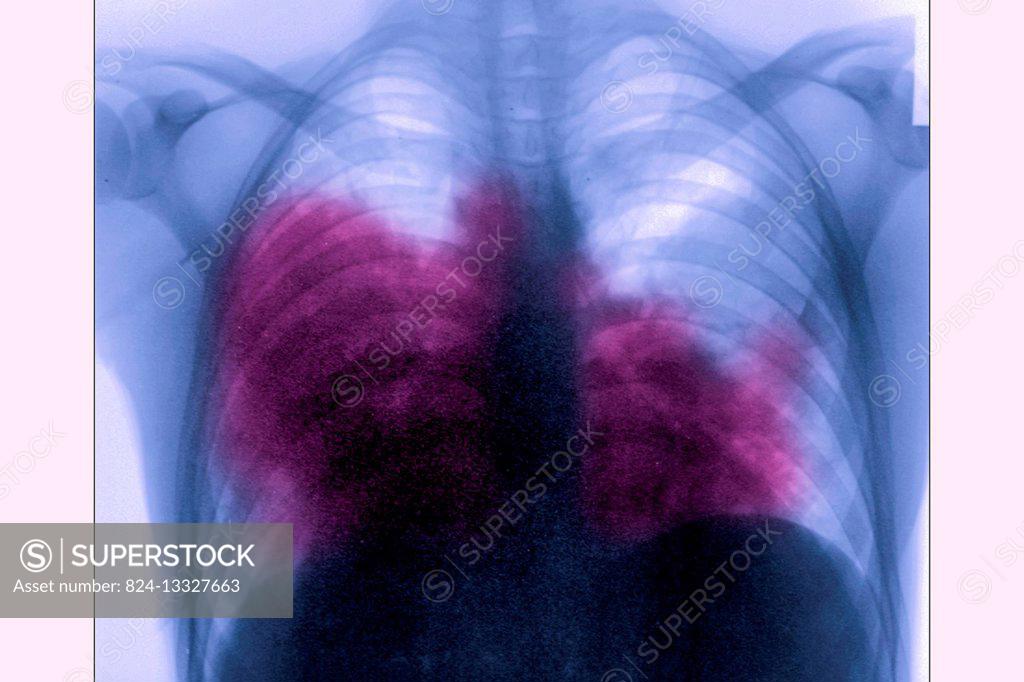

From www.superstock.com

Acute bilateral pneumonia (legionnaires? disease caused by Legionella Is Legionnaires Disease Pneumonia Legionnaires' disease is a serious type of pneumonia caused by legionella bacteria. Legionnaires’ disease is a serious type of pneumonia you get when legionella bacteria infect your lungs. The predominant symptoms of legionnaires disease include. Legionnaires disease is an atypical pneumonia frequently clinically different from other bacterial pneumonia. You can get legionnaires’ disease. It sickens about 5,000 people in the.. Is Legionnaires Disease Pneumonia.